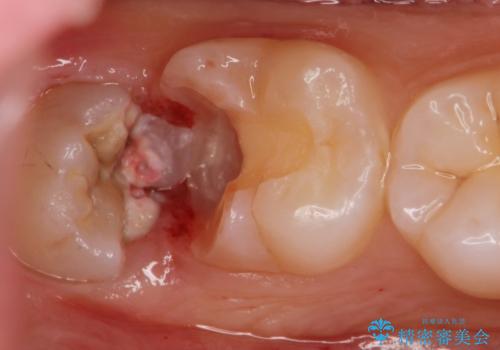

- 親知らずが虫歯になっている気がするとの事で来院。

親知らずとその手前の歯が虫歯になっていました。

先に虫歯を徹底的に取り除き親知らずを抜歯してe-maxインレーで治療を行いました。